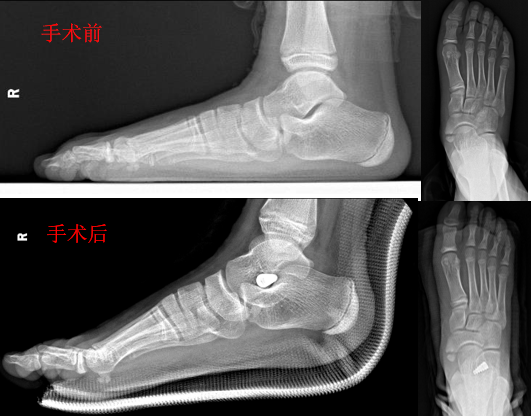

僵硬性平足症,通常需要行早期手术治疗,避免错过最佳治疗机会。对于柔软性平足症,保守治疗效果不佳时,8-13岁是平足手术干预的最佳时机距下关节制动手术是一项简单、可靠、有效而又微创的技术(1.5cm小切口)。

距下关节制动手术

当然还有肌腱松解、软组织重建手术、跟骨截骨术、外侧柱延长术、Cotton 截骨术、关节融合手术等其他手术方式,不同术式有不同的适应症。